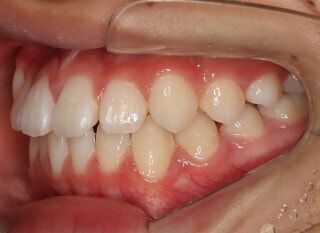

治療前